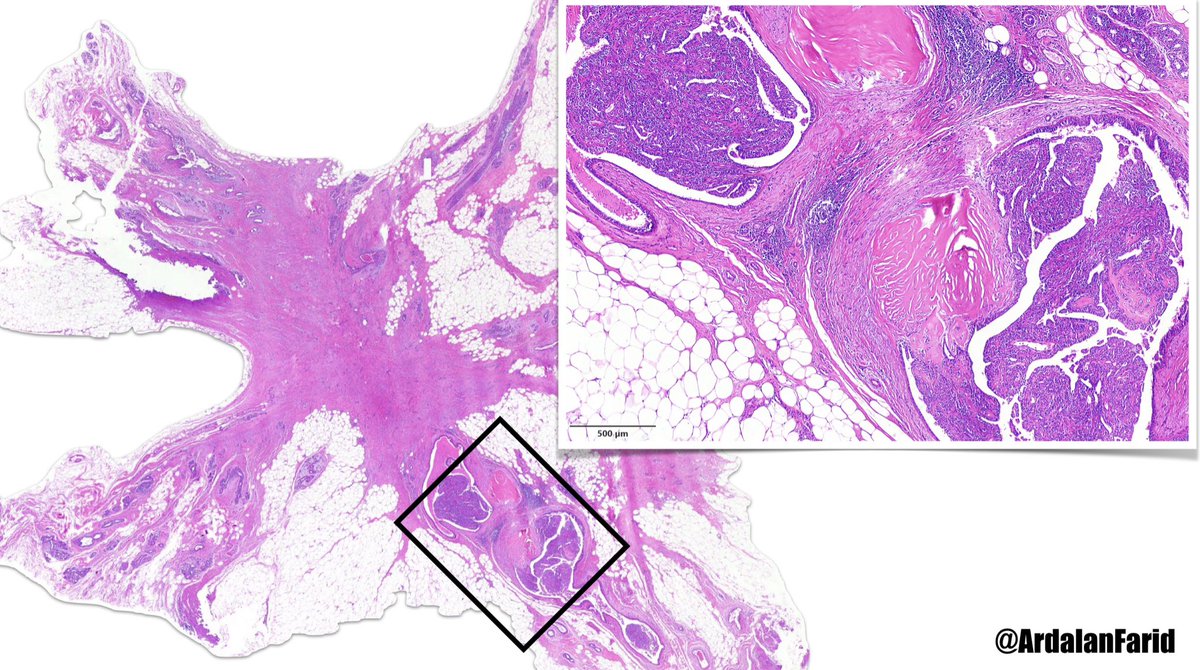

An 84-year-old man with a solitary #lung_mass What’s your #diagnosis? Is it a rare case of P40 and TTF1 co-expression in a #nonsmall_cell_carcinoma or SCC with false positive reaction with #SPT40 clone? Sanjay Mukhopadhyay Andrew Bellizzi 🇺🇦 B.Jahanbin

An 84-year-old man with a solitary #lung_mass

What’s your #diagnosis?

Is it a rare case of P40 and TTF1 co-expression in a #nonsmall_cell_carcinoma or SCC with false positive reaction with #SPT40 clone?

<a href="/smlungpathguy/">Sanjay Mukhopadhyay</a> <a href="/IHC_guy/">Andrew Bellizzi 🇺🇦</a> <a href="/jahanbin_b/">B.Jahanbin</a>